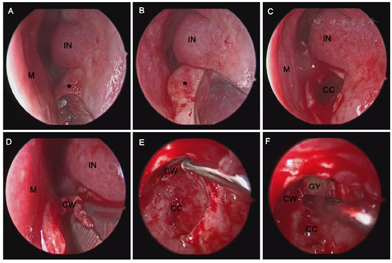

对患者实施鼻内镜下经鼻底开窗术治疗上颌骨含牙囊肿。具体麻醉和手术方法如下患者取平仰卧位,气管插管,静脉给药全身麻醉,常规碘伏消毒铺巾,生理盐水20 ml+1‰肾上腺素3 ml浸润棉片行双侧鼻腔黏膜表面收缩3次,每次5 min。鼻内镜检查左鼻前庭近固有鼻腔底部前外下方见肿物隆起,表面无充血,质地软,未及明显分支。鼻内镜下窦刀沿鼻底隆起处边界U型切开,向后反转囊肿顶壁,取囊肿顶壁黏膜送病检,见大量黄色囊液溢出,清除囊液,70°内镜下见上颌骨囊肿内黏膜光滑,修整及扩大鼻底骨性开口至上颌骨囊肿边缘,外界至上颌窦内下壁骨质,内侧壁至鼻中隔,70°镜下沿囊腔切除突入上颌窦内的囊肿壁,磨除部分上颌窦内下壁骨质,开放上颌窦,电动吸切器修整上颌窦黏膜,使鼻底术腔与上颌窦贯通,使术腔与外界相通,冲洗术腔,彻底止血,创面填塞明胶海绵(图3)。

M:鼻中隔;IN:下鼻甲;CC:囊肿囊腔;CW:囊肿壁;GY:上颌窦腔

患者术中未见鼻泪管损伤,术后未出现溢泪、鼻甲萎缩、坏死、鼻腔干燥及面部麻木等并发症。术后随访3~12个月,下鼻甲形态良好,经开窗的囊腔引流通畅,囊壁黏膜上皮化好,未见开窗闭锁及挛缩。患者颌面部膨隆、肿胀,眼胀、鼻塞、局部压痛等症状逐渐消失(图4)。